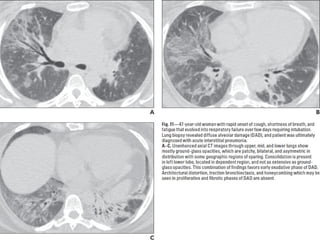

COP

• Ex BOOP

• Asociada a : colágeno, infecciones, EII,

radiación, toxicidad, transplante órganos

Criptogénica: idiopática

55 h=m

4- 6 semanas con síntomas de gripe

Buen pronóstico

COP CT

• Consolidaciones parcheadas

• Broncograma aéreo Signo halo inverso

• Vidrio esmerilado periférico o peribroncovascular

• Crazy paving

• LI

• Nódulos, cavitarse

• Puede simular neumonía

• Reticulación subpleural

• Derrame pleural